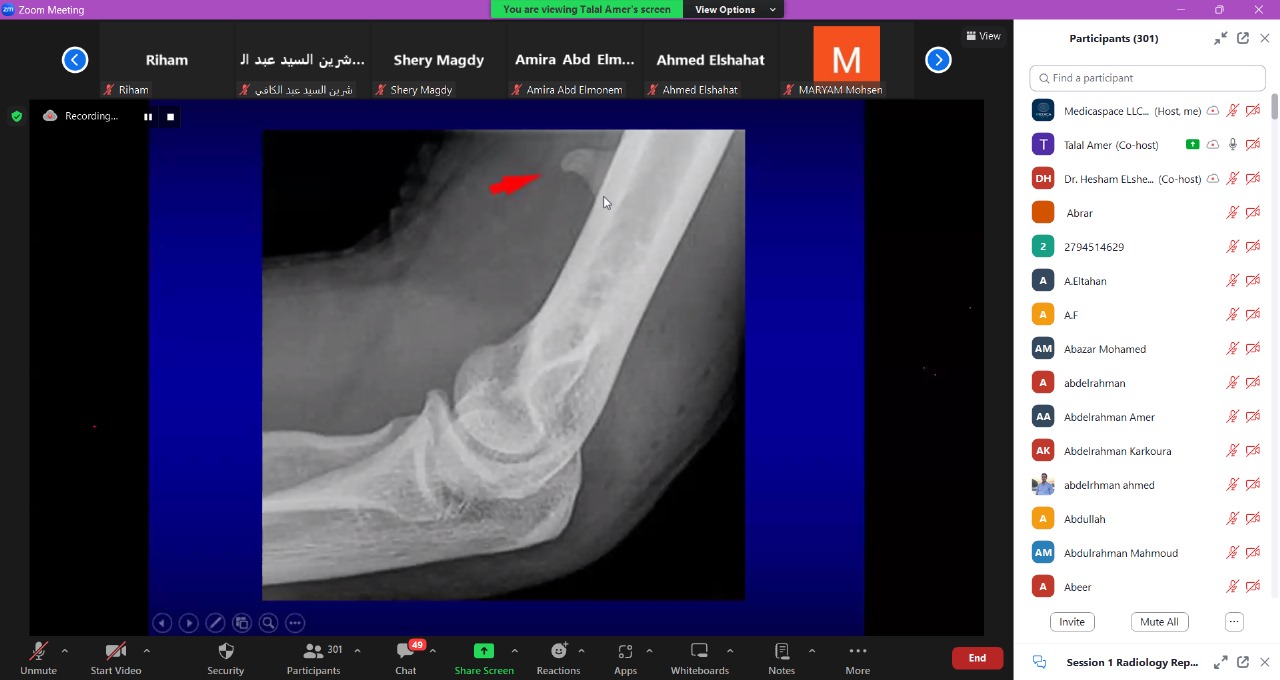

Medicaspace appreciates the effort made to make the radiology reporting course a success.

We are so proud that we are the responsible for organizing this successful course, which was attended by more than 500 individuals. With sincere thanks to the Egyptian society of radiology and all the doctors

Dr. Hesham Elsheikh

Dr. Talal Amer